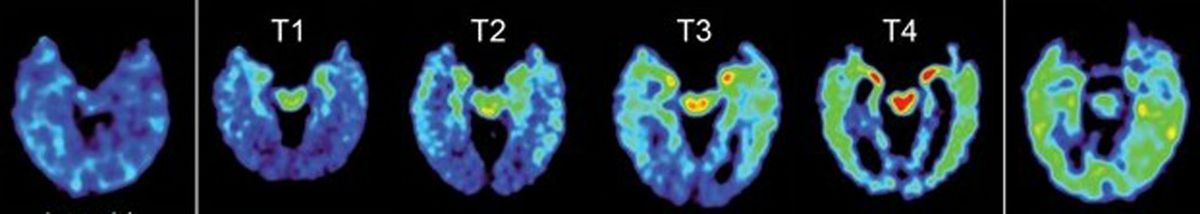

The team identified four stages of deposits that could signify early to advanced levels of CTE.

“These different stages reflected by the brain marker may give us more insight into how CTE develops and allow us to track the disease over time,” said Dr. Vladimir Kepe, an author of the study and a research pharmacologist in molecular and medical pharmacology at the Geffen School of Medicine.

The PET scans revealed that the imaging patterns of the retired football players showed tau deposit patterns consistent with those that have been observed in autopsy studies of people with CTE.

Compared with healthy people and those with Alzheimer’s, the former athletes had higher levels of FDDNP in the amygdala and subcortical regions of the brain, which are areas that control learning, memory, behavior, emotions, and other mental and physical functions.

People with Alzheimer’s, on the other hand, had higher levels of FDDNP in areas of the cerebral cortex that control memory, thinking, attention and other cognitive abilities. And the athletes who had experienced more concussions also had higher FDDNP levels.